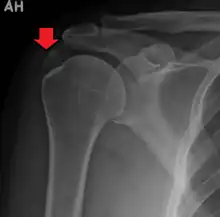

A plain X ray of the shoulder showing calcific tendinitis

An x-ray showing calcific deposits in the area of the tendons of the rotator cuff muscles

Calcific tendinitis is typically diagnosed by physical examination and X-ray imaging.[1] During the formative phase, X-ray images typically reveal calcium deposits with uniform density and a clear margin.[1] In the more painful resorptive phase, deposits instead appear cloudy and with unclear margins.[1] By arthroscopy, formative stage deposits appear crystalline and chalk-like, while resorptive stage deposits appear smooth resembling toothpaste.[1] Ultrasound is also used to locate and assess calcium deposits. In the formative stage, deposits are hyperechoic and arc-shaped; in the resorptive stage deposits are less echogenic and appear fragmented.[1][3]